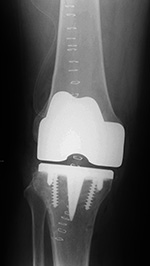

| Unicompartmental knee prosthesis placed in the medial compartment (AP view) |

Unicompartmental knee prosthesis placed in the medial compartment (lateral view) |

| From Taljanovic, 2005 |